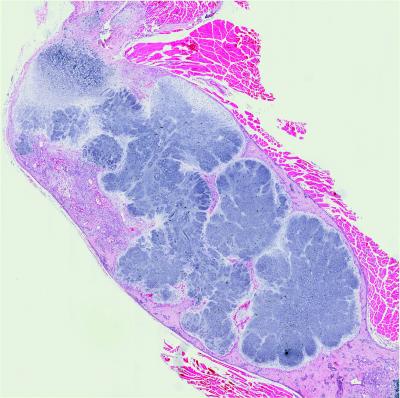

In a developing embryo, many bones form based on cartilage templates. The study found that to form these templates, Lkb1 protein controls the progression of immature, dividing cartilage cells into larger, mature and fully differentiated cartilage cells. Without Lkb1, the population of immature cartilage cells disproportionately increases, leading to skeletal tumors.

The way that Lkb1 controls the differentiation of cartilage cells is by suppressing what's known as the "mammalian target of rapamycin (mTOR) pathway" — a very important complex of molecules that coordinates growth in response to available nutrients and other factors. Problems with the mTOR pathway have been implicated in a host of human diseases, including diabetes, obesity, depression and many cancers.

The influence of abnormal Lkb1 isn't restricted to the skeleton, however. Mutant forms of Lkb1 are frequently present in patients with lung, cervical, breast, intestinal, testicular, pancreatic and skin cancers, and in patients with the Peutz–Jeghers syndrome, characterized by benign polyps in the gastrointestinal tract.